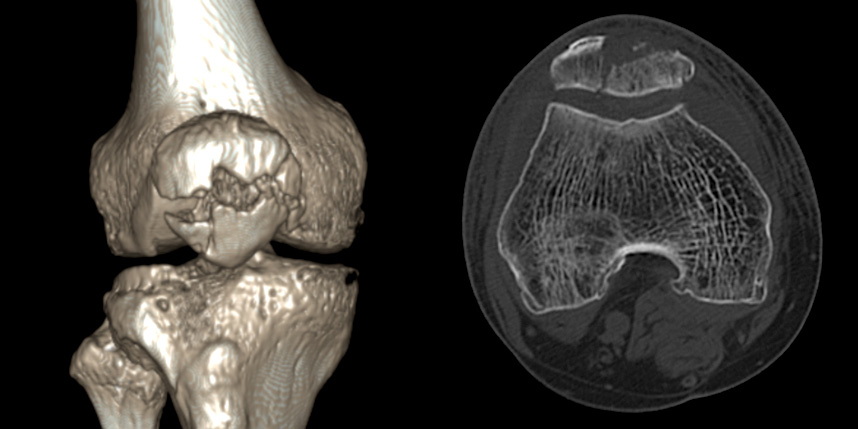

무릎 골절

골절은 정확하게 골절편을 잘 맞추고 고정하는 것이 중요합니다. 특히 관절면을 잘 맞추는 것이 중요합니다.